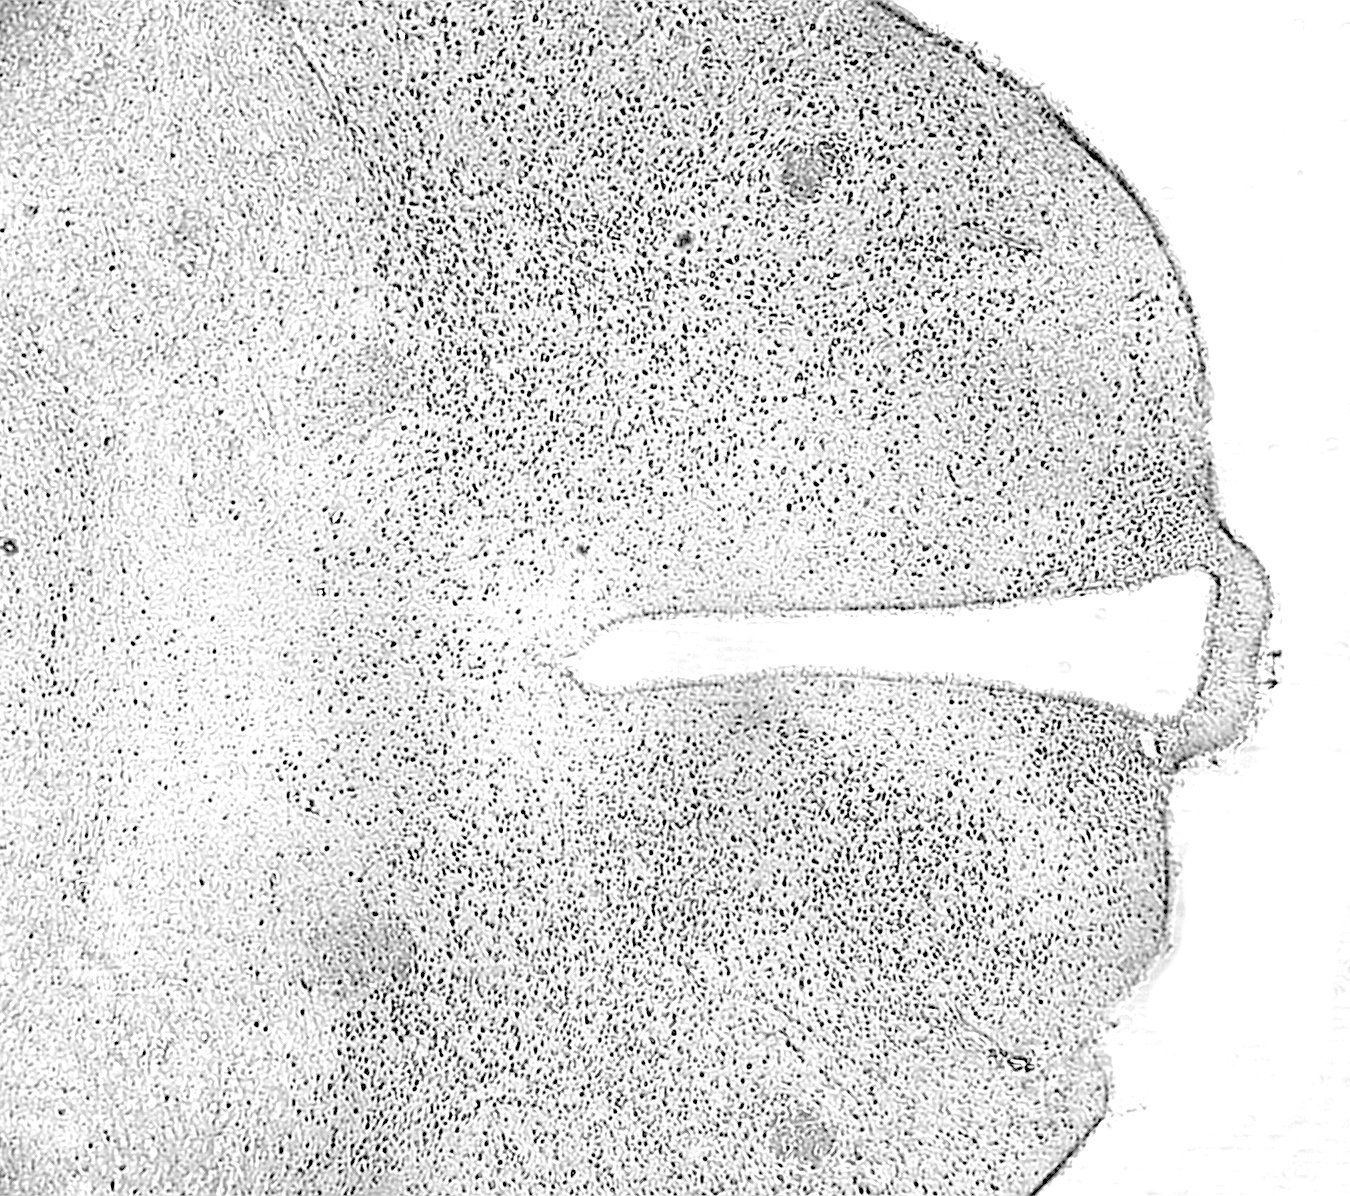

Hóa mô miễn dịch có thể được sử dụng để chẩn đoán ung thư. Các phương pháp chẩn đoán hóa mô miễn dịch sử dụng các kháng thể đặc hiệu để nhận diện các biểu hiện miễn dịch của tế bào ung thư. Việc sử dụng hóa mô miễn dịch trong chẩn đoán có thể giúp xác định loại ung thư, đánh giá mức độ phát triển của bệnh và định hướng điều trị phù hợp.